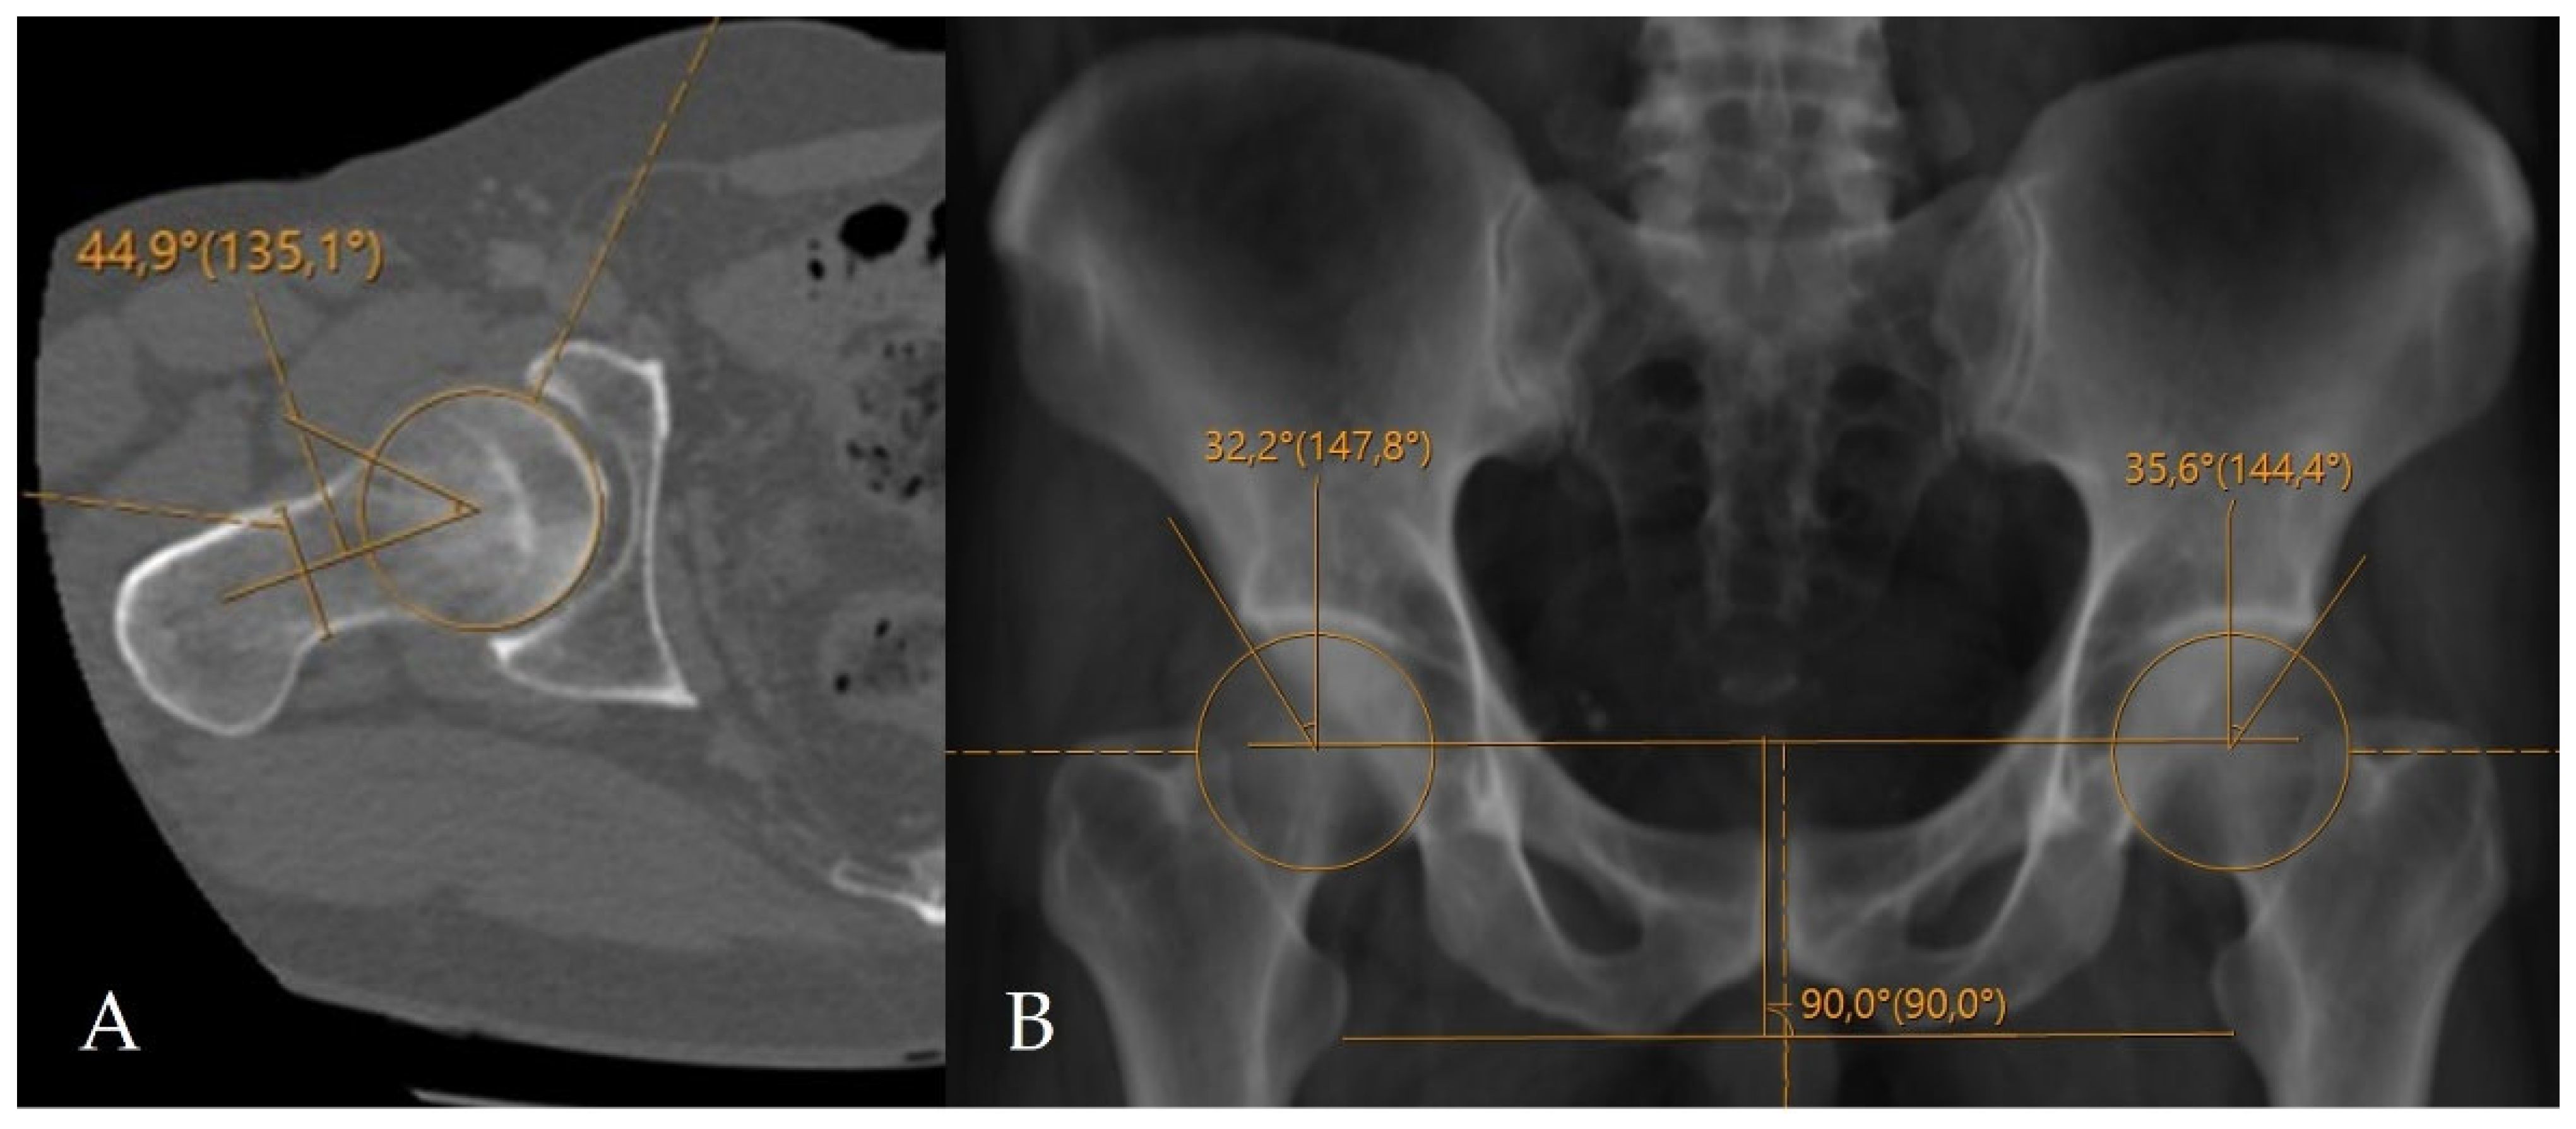

The alpha angle and lateral center–edge angle (LCEA) were measured on CT. The alpha angle was assessed on axial oblique CT reformats parallel to the femoral neck axis as described by Nötzli et al., and the LCEA was measured using the CT-based coronal three-dimensional (3D) virtual pelvis radiograph model as used by Ergen et al. [13,14]. Acetabular coverage index (ACI) values were subsequently calculated using CT-MIP reconstructions. In all cases, angular measurements were complemented by a comprehensive morphological assessment for the presence of FAI, including evaluation of the crossover sign, posterior wall sign, ischial spine sign, and anterior wall lateralization (Figure 2 and Figure 3). CT was further used to evaluate the morphology of the acetabular rim, and acetabular overcoverage subtypes were determined [15]. The presence of underlying FAI and its specific subtype were determined by two radiologists in consensus. All measurements were independently repeated by both radiologists at a four-week interval. The senior radiologist had 20 years of musculoskeletal radiology experience, whereas the general radiologist had 5 years of clinical radiology experience. Prior to the measurements, the general radiologist underwent a one-week training period under the supervision of the senior radiologist. Statistical analyses were performed using the measurements obtained by the senior musculoskeletal radiologist. To assess intraobserver reliability, the senior radiologist recalculated ACI measurements after a minimum interval of two months. Prior to initiating angular measurements, the entire dataset was reviewed and verified by an independent radiology resident after deletion of all previous measurements and anonymization of cases. Subsequently, cases were randomly ordered to minimize assessment bias and ensure objective analysis. For primary statistical analyses, measurements obtained by the senior musculoskeletal radiologist were used to reflect routine clinical practice, while the second reader’s measurements were used exclusively for interobserver agreement analysis.

Figure 2.

Application of conventional angular measurement methods on a radiology workstation. (A) Measurement of the alpha angle on axial oblique CT reformats. (B) Measurement of the LCEA on a CT-based virtual pelvic radiograph.

Figure 3.

Assessment of additional morphological parameters of femoroacetabular impingement on a CT-based virtual pelvic radiograph. (A) Negative acetabular crossover sign. The black solid line represents the posterior acetabular wall, and the black dashed line represents the anterior acetabular wall. (B) Positive acetabular crossover sign with an associated ischial spine sign (white arrow), suggestive of pincer-type femoroacetabular impingement and acetabular retroversion.